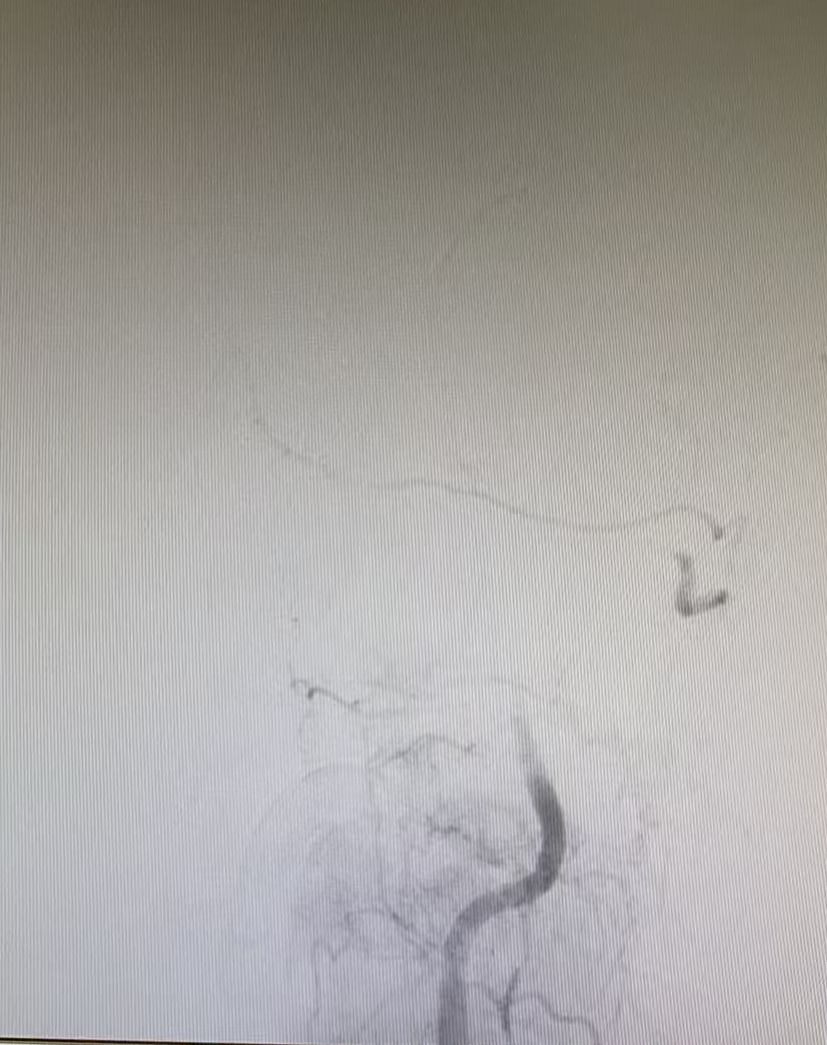

與家屬充分溝通并取得同意后,晚上7點(diǎn)42分,患者被推入介入手術(shù)室。手術(shù)團(tuán)隊(duì)經(jīng)驗(yàn)豐富,操作精準(zhǔn),晚上7點(diǎn)50分成功建立手術(shù)通路,在DSA影像引導(dǎo)下,微導(dǎo)絲與微導(dǎo)管精準(zhǔn)穿越閉塞血管段。晚上8點(diǎn)07分,堵塞的椎基底動(dòng)脈被成功開通,從進(jìn)入介入室到血管再通,僅用時(shí)25分鐘。

但挑戰(zhàn)還在繼續(xù),血管開通后發(fā)現(xiàn)內(nèi)部存在嚴(yán)重狹窄,遠(yuǎn)端血流灌注不足,團(tuán)隊(duì)隨即進(jìn)行球囊擴(kuò)張改善血流,但血管回縮明顯。為確保持久通暢,團(tuán)隊(duì)果斷植入一枚支架。最終,血管形態(tài)恢復(fù)良好,血流達(dá)到最佳標(biāo)準(zhǔn),缺血的大腦獲得了充足的血液供應(yīng)。

術(shù)前血管閉塞

球囊擴(kuò)張術(shù)后

支架置入后